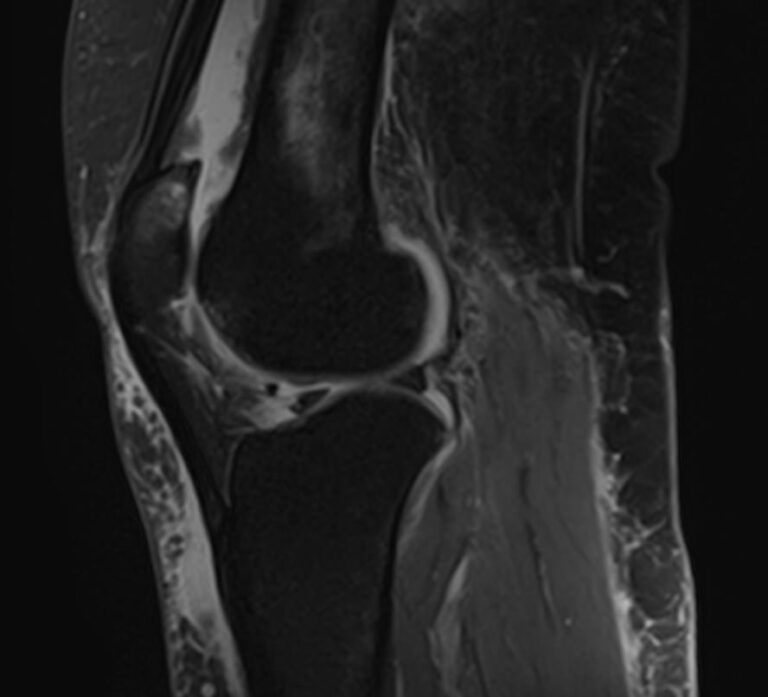

При сочетанном поражении этих анатомических областей целесообразно проведение комплексной МРТ, включающей обследование пояснично-крестцового отдела позвоночника и коленных суставов.

Магнитно-резонансная томография является высокоинформативным методом выявления причин возникновения заболеваний позвоночного столба и суставов. В клинике «Доступная медицина» диагностика осуществляется на новейшем высокопольном томографе закрытого типа TOSHIBA VANTAGE TITAN 1,5 Тесла, обеспечивающем высочайшее качество изображений исследуемой зоны.

Томограф позволяет детально визуализировать состояние всех анатомических структур позвоночного столба на исследуемом уровне, костные структуры колена и окружающие мягкие ткани данных анатомических областей, включая мышцы, связки, нервные сплетение, сосуды.